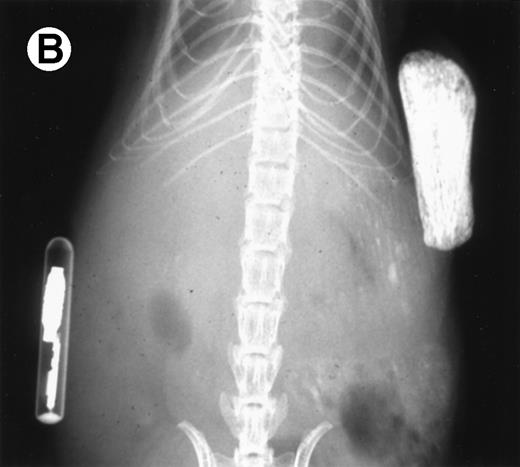

Growth of the myeloma cells was associated with increased blood Ca levels (summarized in Fig 5), suggesting anomalies in bone remodeling. Immunohistochemical examination of the kidneys showed varying amounts of light chain deposits (not shown). Decalcified bone sections stained for TRAP showed markedly increased osteoclast activity (Fig 6). Severe loss in human bone density was readily visible upon x-ray examination in all cases. Although density loss was severe in all mice, the degree of human bone resorption varied. An example depicting a moderate level of density loss is presented in Fig 7.

Loss in density of human bone in myeloma-bearing SCID-hu mouse as seen by x-radiography. Human bones are visible in the right-hand side. The highly contrasted devices visible in the bottom left corner are implant transponders used to identify the mice. (A) Myeloma-bearing mouse (patient no. 6): (B) Age-matched control SCID-hu mouse.